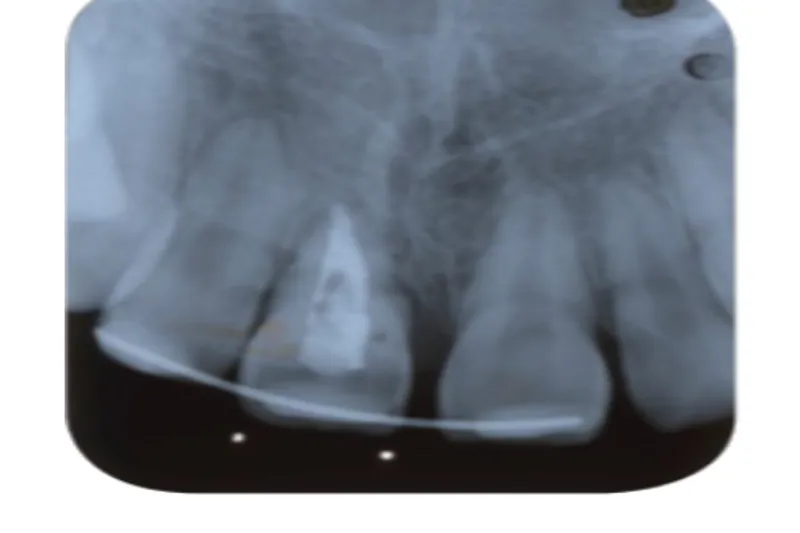

En 10-årig pige eksartikulerede 1+, som blev replanteret på skadestuen efter ca. en time.

Tanden ankyloserede og var tre år efter traumet i ca. 2 mm infraposition.

Der blev foretaget kirurgisk ekstrusion med tang til normal position, og tanden blev fikseret med en elastisk ortodontisk buetråd i to uger.